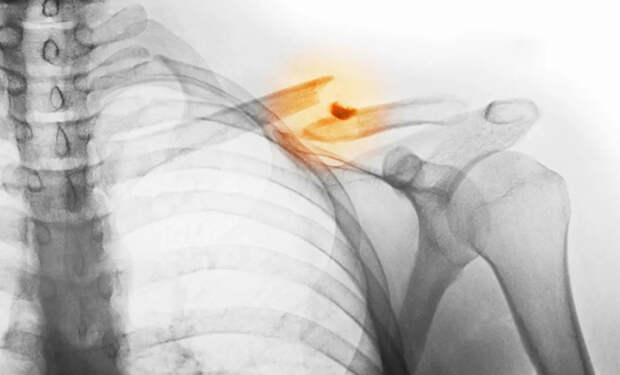

Главное преимущество метода в том, что отпадает необходимость изготавливать имплант заранее. Обычно донорскую кость или металлическую вставку приходится долго подгонять по форме. Новый же подход позволяет напечатать трансплантат прямо в ране за считанные минуты.

Вместо клея в пистолет загружается комбинация гидроксиапатита — вещества, которое содержится в костях, — и биосовместимого поликапролактона. Этот пластик плавится при низкой температуре и безопасен для тканей. Меняя пропорции компонентов, врач может регулировать прочность и жесткость вставки прямо в процессе печати.

Компактность устройства позволяет врачу вручную контролировать угол, направление и глубину печати. По словам ученых, процедура занимает всего несколько минут, что существенно сокращает время операции и снижает риски.